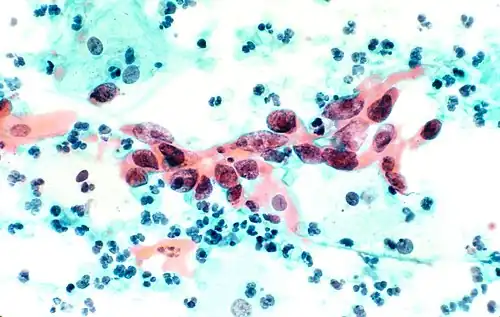

В результате окрашивания по Папаниколау клетки остаются прозрачными. Ядра клеток принимают цвет от синего до чёрного. Цитоплазма окрашивается в сине-зеленый цвет; кератин — в оранжевый.

Эозин Y окрашивает поверхностный плоский эпителий, ядрышки, реснички и эритроциты. Светло-зеленый SF желтоватый придает голубое окрашивание цитоплазме призматических, парабазальных плоских и промежуточных плоских клеток. Поверхностные клетки окрашиваются от оранжевого до розового, а промежуточные и парабазальные клетки становятся бирюзово-зелеными или голубыми[6].

Клетки меланомы, тонкоигольная аспирационная пункционная биопсия печени.